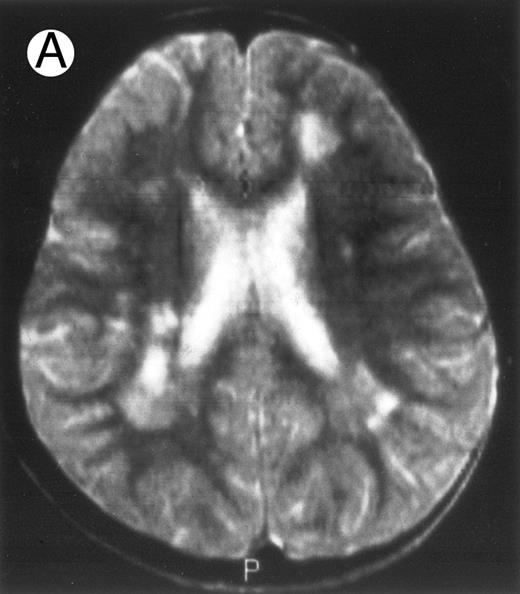

Together, 19 patients had primary severe CNS disease progression or CNS relapse (Fig 1). Three of 19 had a CNS relapse characterized by meningitis only. Neurological symptoms occurred in 16 of these 19 patients (9 from the onset and 7 after the initial meningitis) (Fig 1). No clinical or neuroradiological difference was detected between the patients who developed neurological symptoms as the initial CNS manifestation or after initial meningitis (Table 1). The occurrence of these neurological manifestations marked a turning point in the evolution of the disease, as chemotherapy led to an improvement of the neurological symptoms in only three patients despite the use of intensive treatment by MTX IT. In these three patients, neurological sequelae persisted after the first symptoms and a relapse occurred within 3 to 10 months. Brain imaging was repeated during chemotherapy for four patients with progression of the CNS disease: in three patients, a severe brain atrophy developed (Fig 3A and B) and in the last patient who initially had contrast enhancement in cerebellar white matter, a cerebellum parenchymal loss was observed (Fig 2C). All of these 19 patients treated by chemotherapy only (n = 15) died during a last episode of coma and brain stem symptoms associated with a systemic hemophagocytic syndrome, 6 ± 6 months after the first neurological symptom (irrespective of the age at this first event). Four of these 19 patients were transplanted (one patient received an HLA-identical BMT, three an HLA-partially identical BMT). Median delay between diagnosis and BMT was 14 months (range, 2 to 20 months). All of these four patients died of BMT-related toxicity and/or disease progression.

Evolution of brain lesions during HLH. (A) MRI of a 41/2-year-old girl showing focal white matter hypersignal on T2-weighted images. (B) MRI of the same child 1 year later with an important atrophy of both the white matter and the cortices.